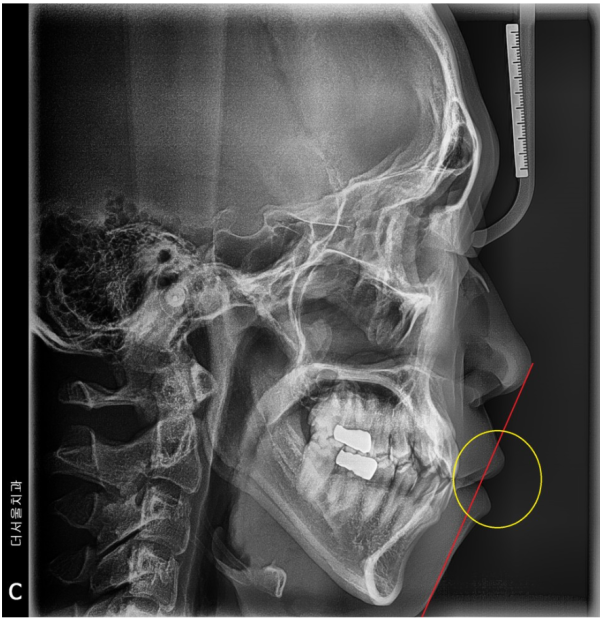

환자분의 얼굴을 옆에서 찍은 세팔로(Ceph)사진을 확인해보겠습니다.

빨간색 선이 코 끝과 턱 끝을 이은 '리케츠라인'입니다.

이 라인보다 입이 튀어나와 있으면 돌출입이라고 하는데요.

개선의 필요성이 있는 상태로 볼 수 있습니다.

Let's take a look at the Ceph picture of your face.

The red line connects the tip of the nose and the tip of the chin.

If your mouth sticks out more than this line, it's called a protruding mouth.

It can be seen as a condition where there is a need for improvement.